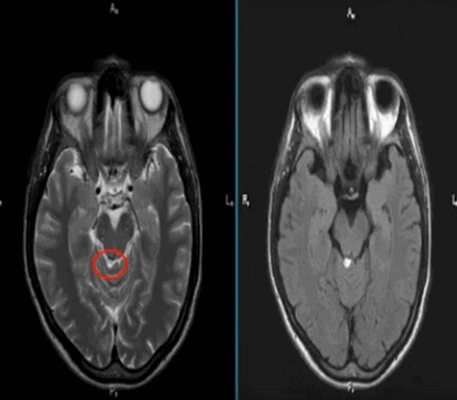

![Липома четверохолмной цистерны на МРТ]()

Липома четверохолмной цистерны на МРТ (обведена кругом)